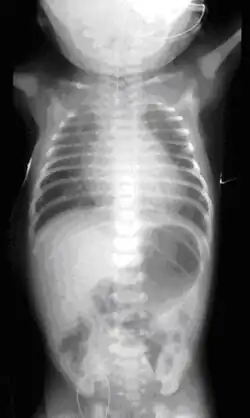

Plain x-ray with contrast in the upper esophagus above the atresia.

If any of the above signs/symptoms are noticed, a catheter is gently passed into the esophagus to check for resistance. If resistance is noted, other studies will be done to confirm the diagnosis. A catheter can be inserted and will show up as white on a regular x-ray film to demonstrate the blind pouch ending. Sometimes a small amount of barium (chalk-like liquid) is placed through the mouth to diagnose the problems. However, performing such an oral contrast study is not advised due to a risk of aspiration.[30]